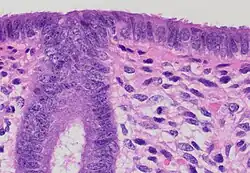

(A) proliferative endometrium (Left: HE × 400) and proliferative endometrial cells (Right: HE × 100)

(B) secretory endometrium (Left: HE × 10) and secretory endometrial cells (Right: HE × 10)

(C) atrophic endometrium (Left: HE × 10) and atrophic endometrial cells (Right: HE × 10)

(D) mixed endometrium (Left: HE × 10) and mixed endometrial cells (Right: HE × 10)

(E): endometrial atypical hyperplasia (Left: HE × 10) and endometrial atypical cells (Right: HE × 200)

(F) endometrial carcinoma (Left: HE × 400) and endometrial cancer cells (Right: HE × 400).